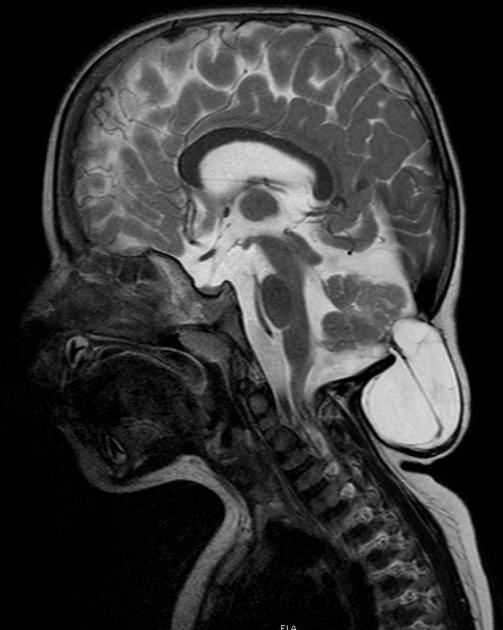

Diagnosis?

Chiari III.

Difference between Chiari II and III?

II- myelomeningocele

III- encephalocele